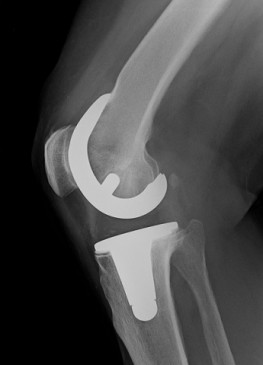

Meine Patientin, 72 Jahre alt, Rentnerin wurde wegen schwerer Kniegelenksarthrose eine Totalendoprothese in das rechte Knie eingesetzt.

Bereits kurze Zeit später treten allerdings ohne ersichtlichen Grund starke Schmerzen über dem Schienbein und dem Sprunggelenk bis ins Knie und Oberschenkel ziehend auf. Diese post-operativen Knieschmerzen erlebe ich häufig in meiner Praxis. Am vernarbten Kniegelenk entwickelt sich eine Arthrofibrose.

Verschiedenste Kontrolluntersuchungen wie Röntgen, MRT, Szintigramm, Labor ergeben keinen ersichtlichen Grund – die Beschwerden nehmen zu.